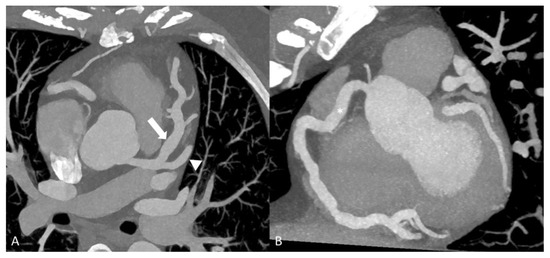

2.2.2. Kawasaki Disease